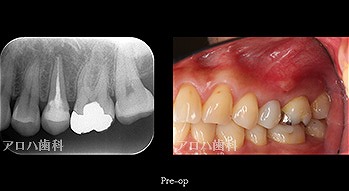

case5

左:頬側よりGP挿入。MB根尖の透過像と一致。

P根にも透過像。穿孔を疑う。

左:術前

右:術後1年

P根の穿孔封鎖

頬側の瘻孔